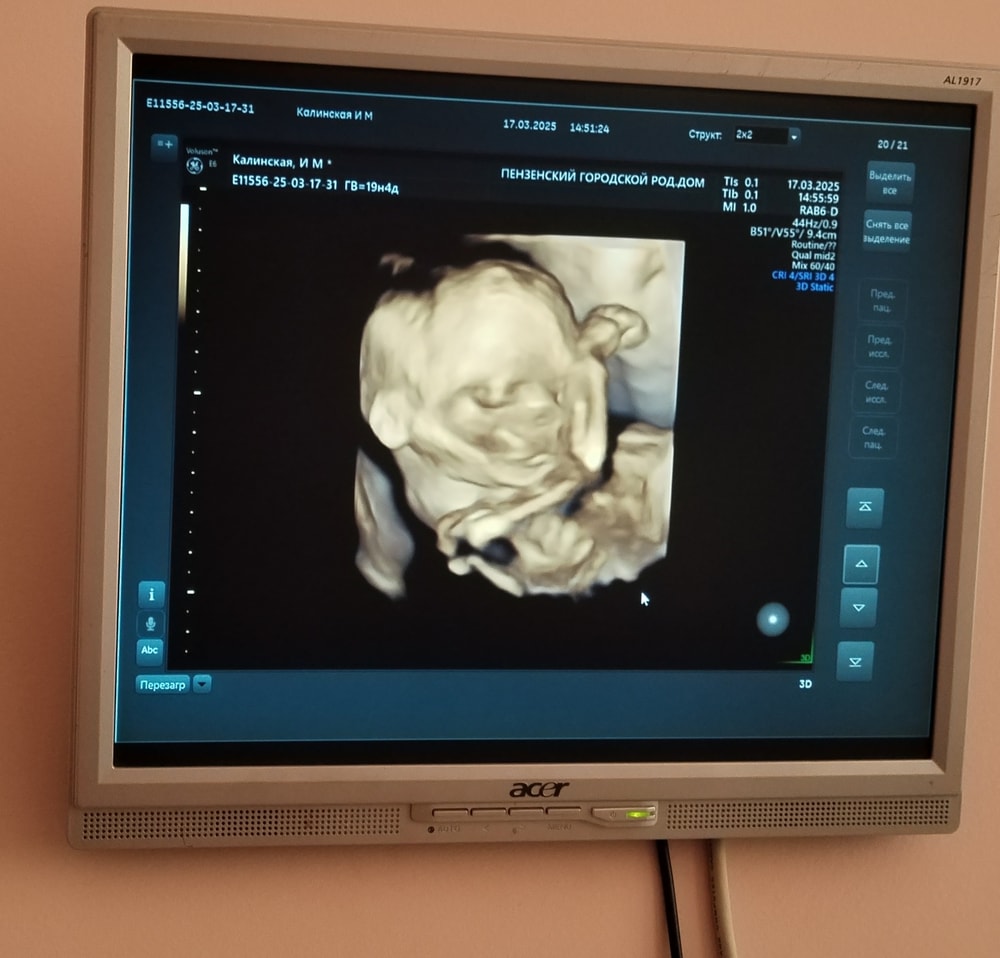

На втором скринге (в 20 недель и 4 дня) подтвердили пол. Будет мальчишка. Вес у него уже 395 грамм, что соответствует ровно 21 неделе. Мы опять опережаем срок🤗. Также делали Эхо кг. Ребёнок полностью здоров.